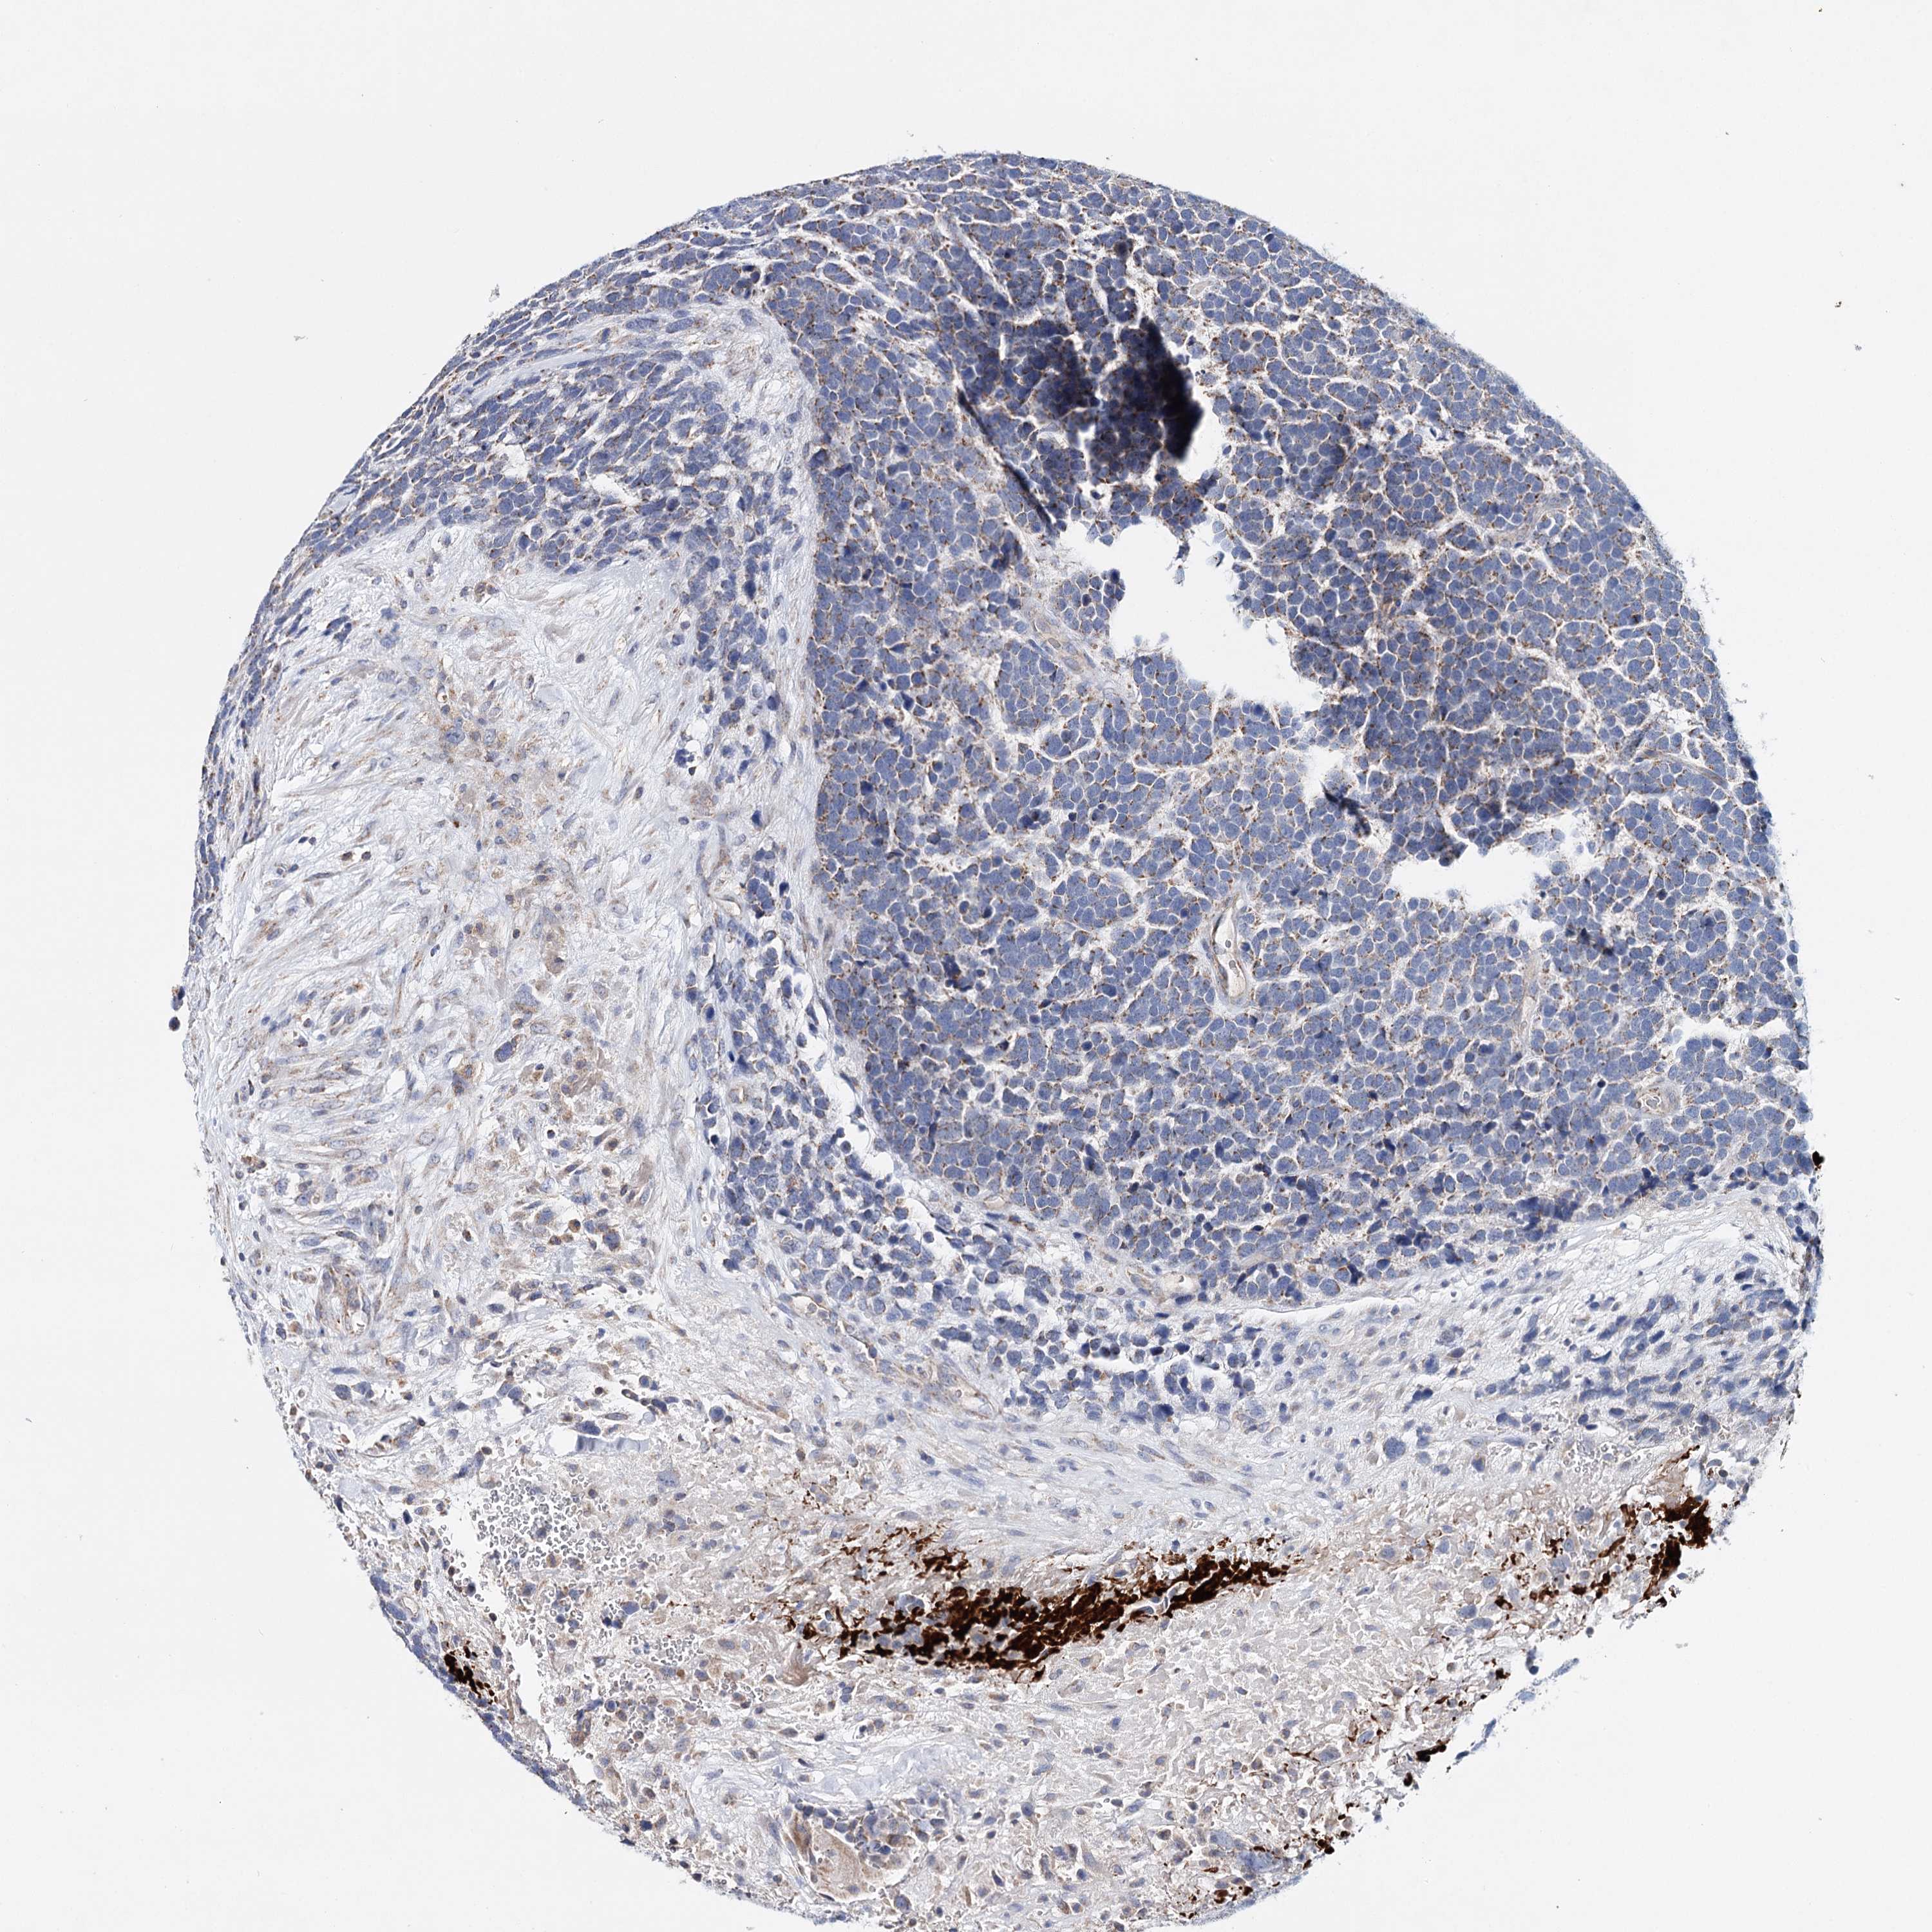

UROTHELIAL CANCER - Protein expressioni

A mouse-over function shows sample information and annotation data. Click on an image to view it in a full screen mode. Samples can be filtered based on level of antibody staining by selecting one or several of the following categories: high, medium, low and not detected. The assay and annotation is described here.

Note that samples used for immunohistochemistry by the Human Protein Atlas do not correspond to samples in the TCGA dataset.

Antibody stainingi

Antibody staining in the annotated cell types in the current human tissue is reported as not detected, low, medium, or high, based on conventional immunohistochemistry profiling in selected tissues. This score is based on the combination of the staining intensity and fraction of stained cells.

Each image is clickable and will lead to virtual microscopy that enables deeper exploration of all samples and also displays staining intensity scores, fraction scores and subcellular localization as well as patient and tissue information for each sample.

Antibody HPA037786

Antibody HPA038034

Antibody HPA038867

Antibody HPA038868

Staining

High

Medium

Low

Not detected

Intensity

Strong

Moderate

Weak

Negative

Quantity

>75%

75%-25%

<25%

None

Location

Nuclear

Cytoplasmic/membranous

Cytoplasmic/membranous,nuclear

Urothelial carcinoma, High grade

Urothelial carcinoma, Low grade

Urothelial carcinoma, NOS